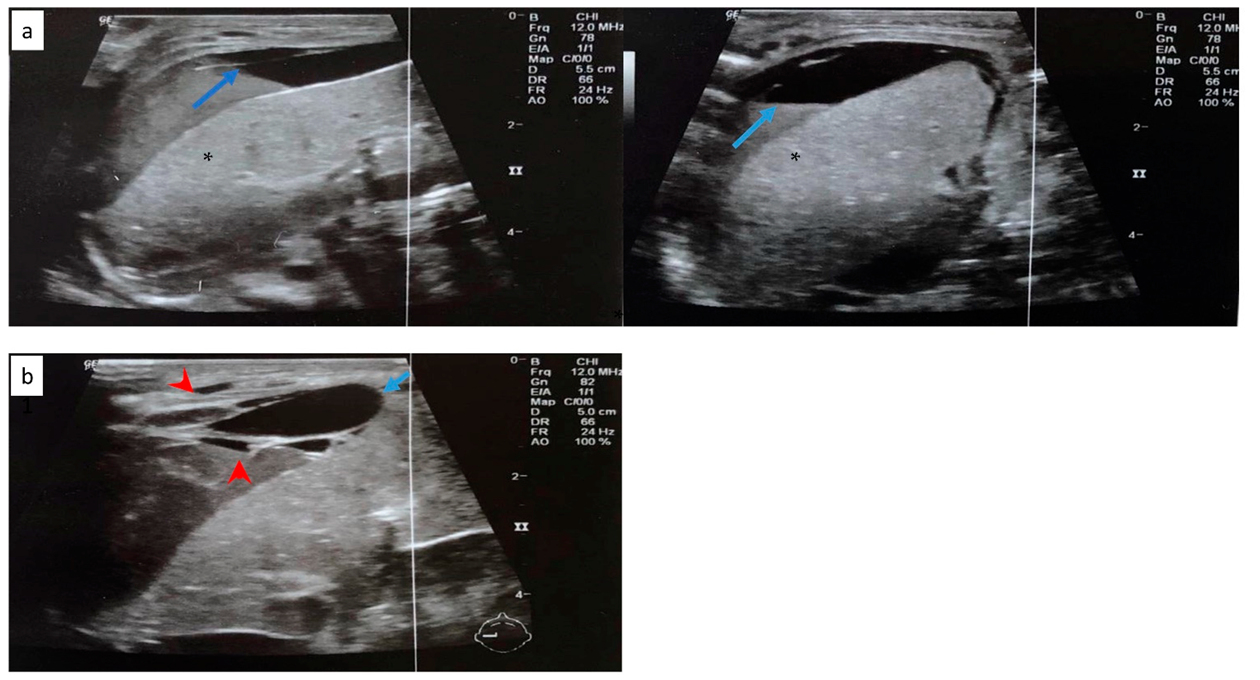

2.2. Case 2